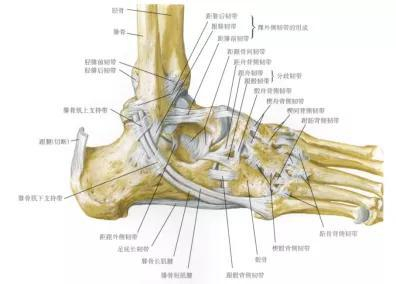

图4 踝关节骨与韧带示意图 图片来源:奈特人体解剖学图谱